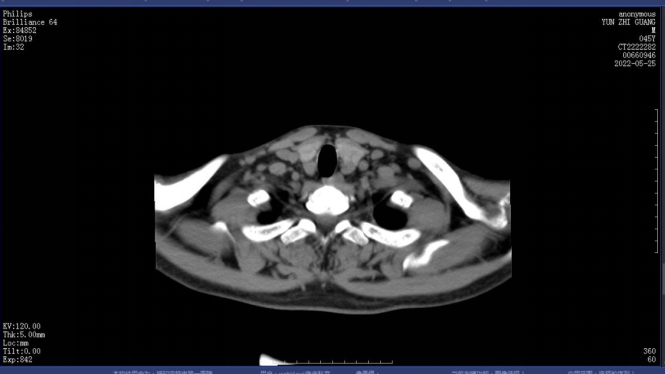

图4.1.术前甲状旁腺CT定位

图4.2.术前甲状旁腺CT定位